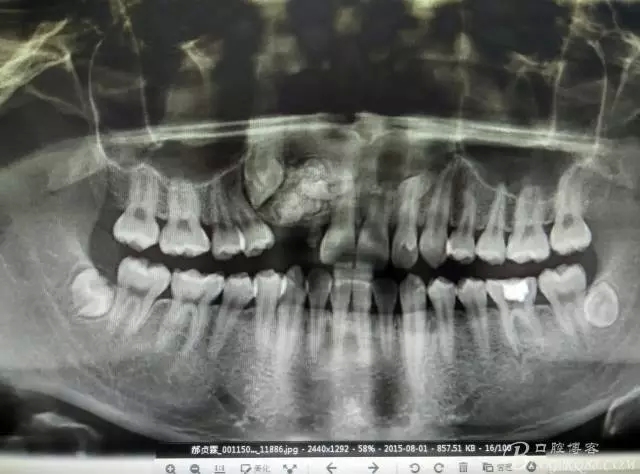

患者、郝xx、男、18歲,主訴:右側(cè)前牙未萌出,要求治療。??茩z查:右上乳Ⅱ滯留,牙冠變色,無(wú)松動(dòng)。12、13未見(jiàn)萌出。對(duì)側(cè)22、23正常萌出。缺牙區(qū)骨性隆起,表面不光滑,質(zhì)地堅(jiān)硬。范圍占有12、13區(qū)域。x全景片檢查:12、13阻生,其冠方有一團(tuán)2.5cmx1.8cm大小的致密團(tuán)塊,里面大小不等。不規(guī)則疑似牙齒影。診斷:牙瘤。處理:建議手術(shù) 摘除牙瘤。

圖1.術(shù)前患者口內(nèi)影像檢查:右上乳Ⅱ滯留,12、13未萌出。粘膜表面觸診有骨性隆起并且凹凸不規(guī)則。

圖2.全景片影像檢查:13阻生,其冠方有重疊影像,其冠方近中上方有一巨大致密鈣化團(tuán)塊。12看不見(jiàn)其蹤影。